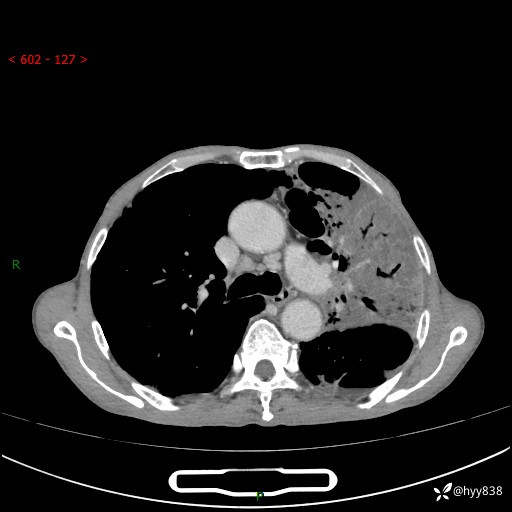

老年男性,反复咳嗽、咳痰、气喘10余年,再发3天。大叶性实变+胸膜病变-结果公布

胸部CT平扫+增强